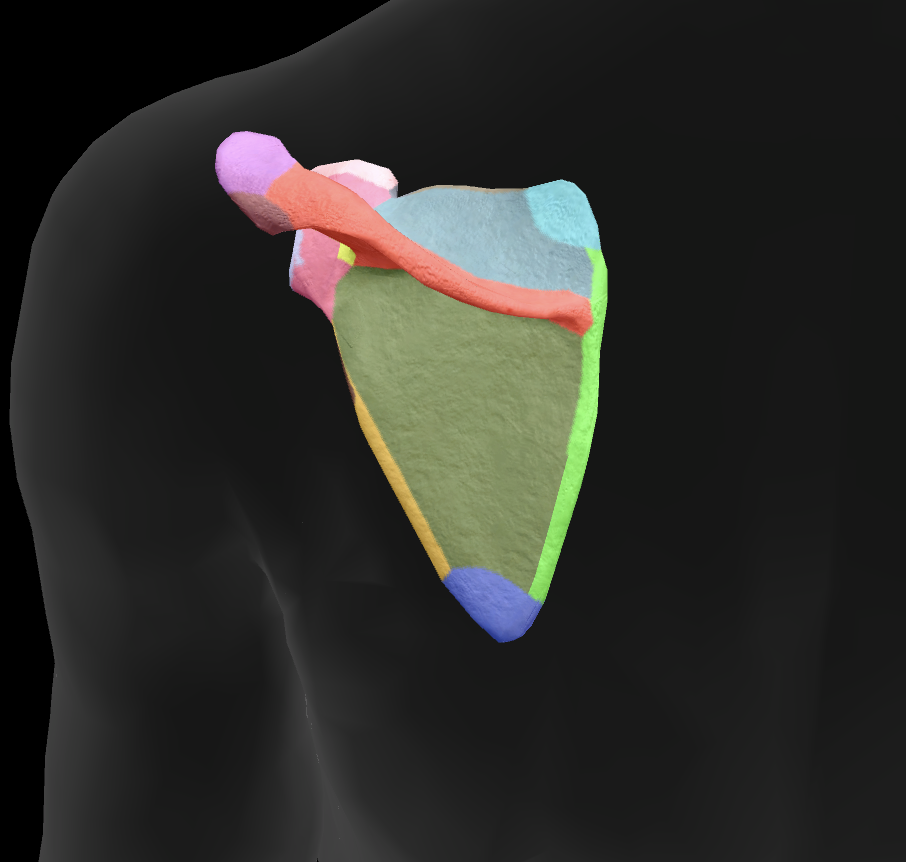

What bone is this?

scapula

What is this boney landmark?

spine of scapula

What is this boney landmark?

supraspinous fossa

What is this boney landmark?

infraspinous fossa

What is this boney landmark?

acromion process

What is this boney landmark?

superior angle

What is this boney landmark?

inferior angle

What is this boney landmark?

lateral border

What is this boney landmark?

medial border

What is this boney landmark?

subscapular fossa

What is this boney landmark?

spinoglenoid notch

What is this boney landmark?

glenoid fossa

What is this boney landmark?

supraglenoid tubercle

What is this boney landmark?

infraglenoid tubercle

What is this boney landmark?

coracoid process